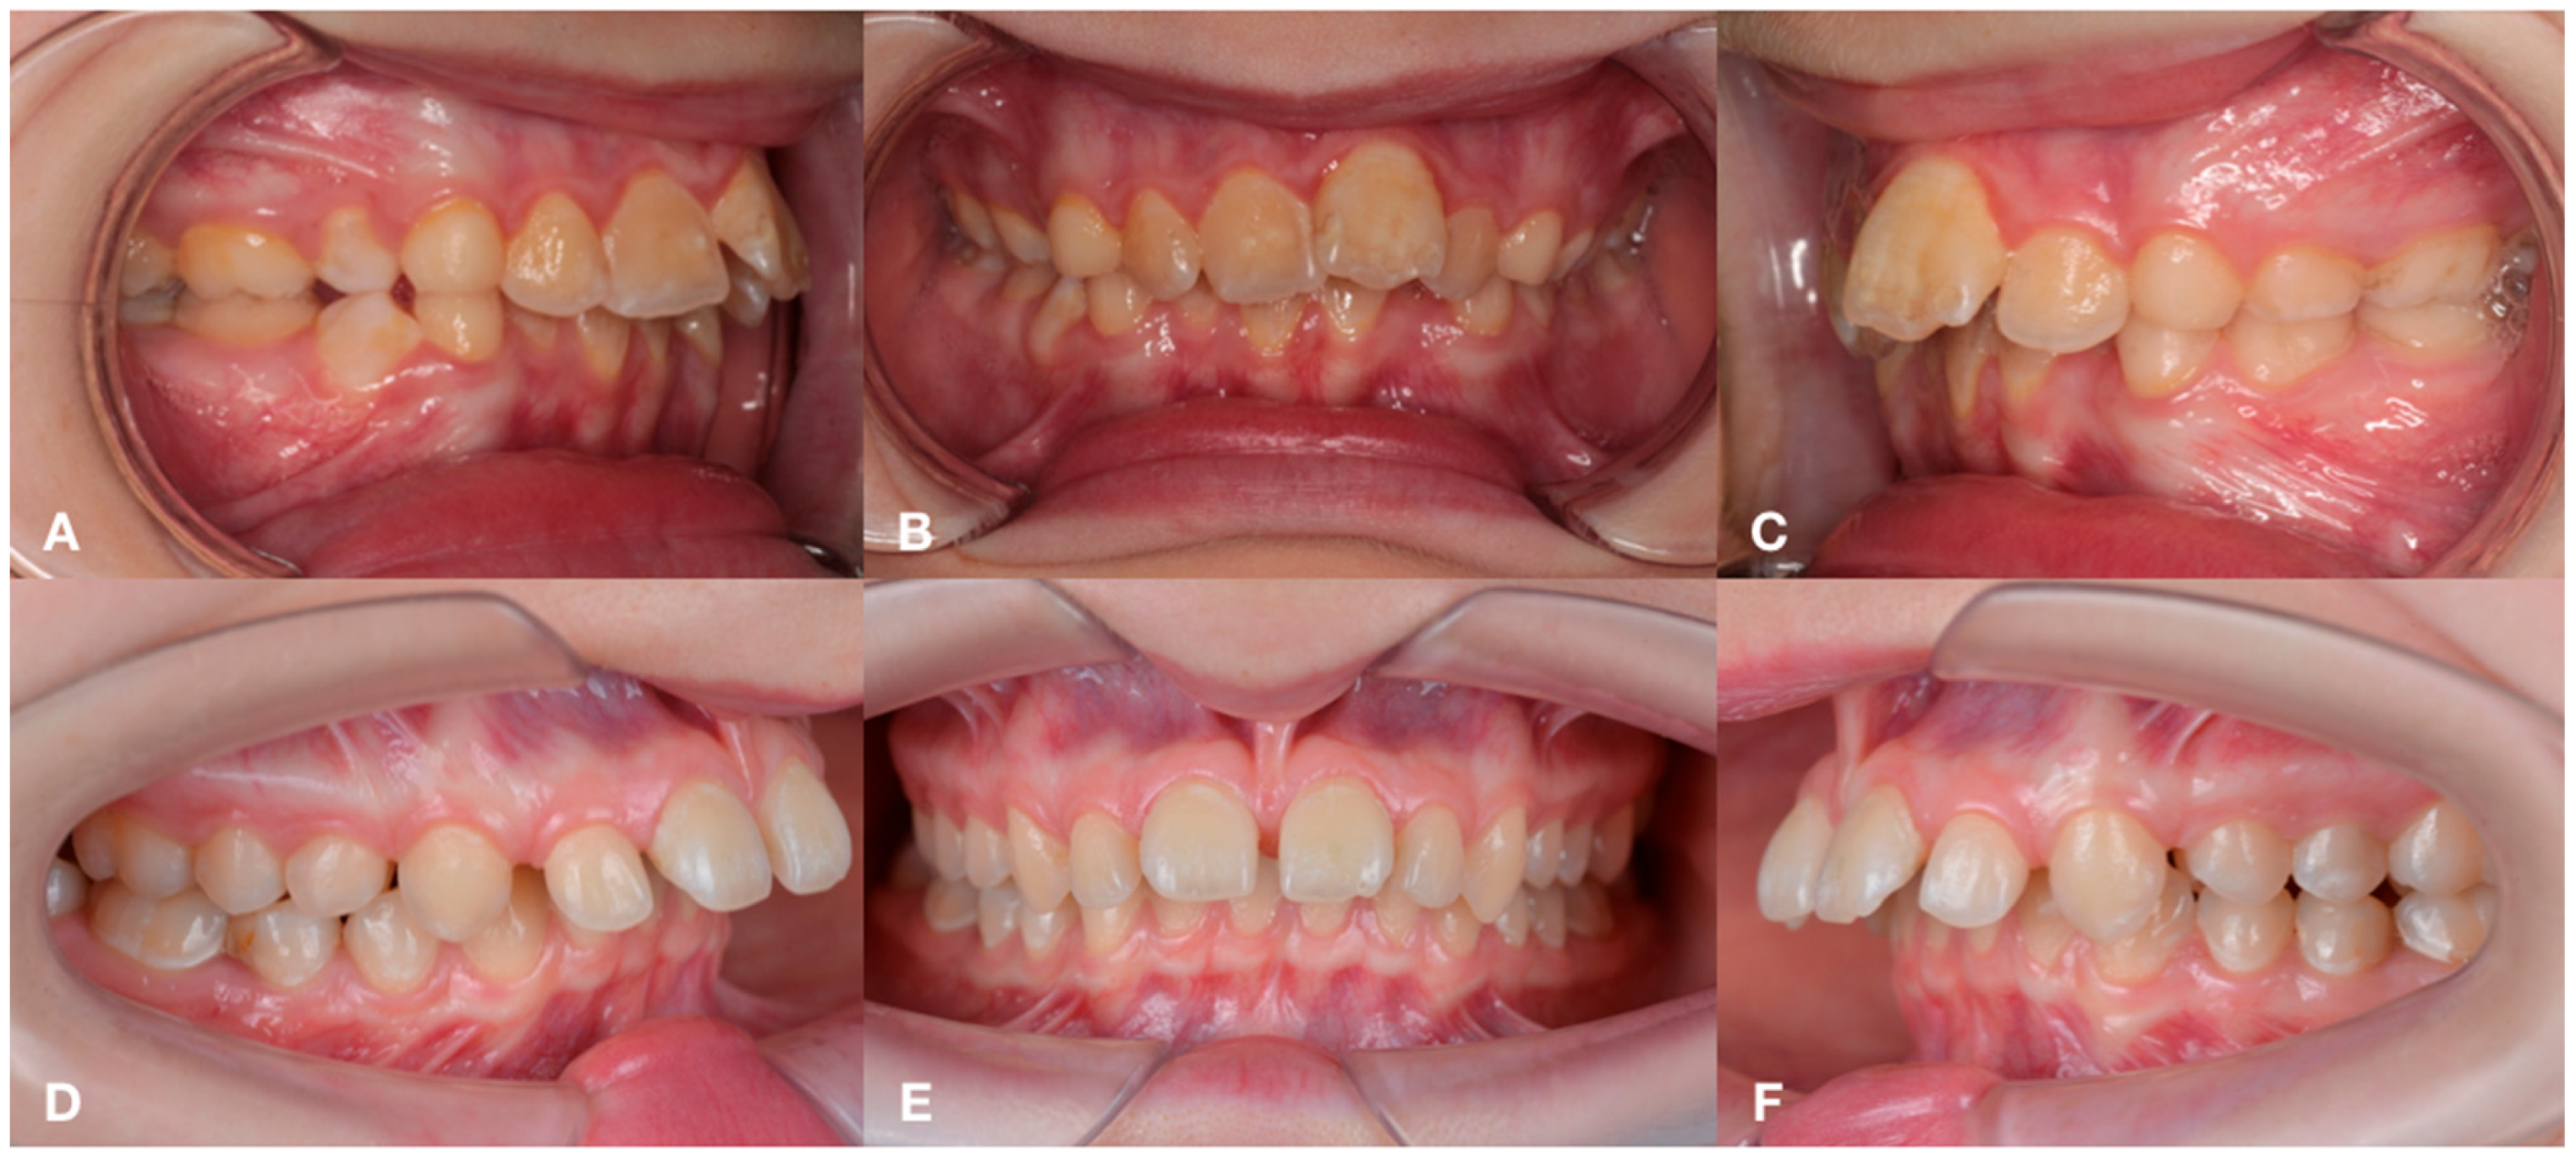

2.1. Subjects

3.1. Periodontal Status and Inflammatory Indices